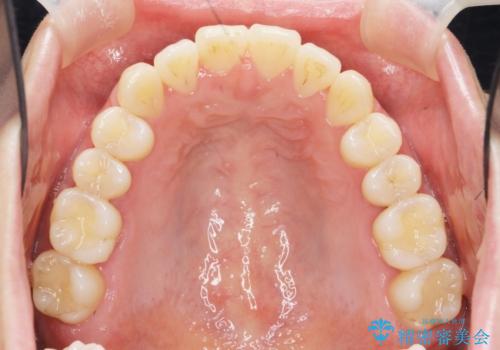

前歯のねじれを改善 マウスピース矯正インビザライン

左側の奥歯は後方移動を行うことで、理想的な噛み合わせに整えるとともに、前歯の突出感も同時に改善することができました。